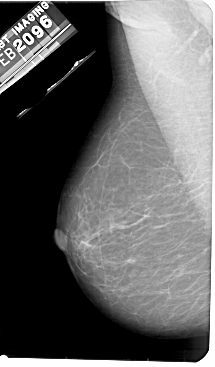

A_1871_1.LEFT_CC

LEFT_CC LINES 5401 PIXELS_PER_LINE 2926 BITS_PER_PIXEL 12 RESOLUTION 43.5 NON_OVERLAY